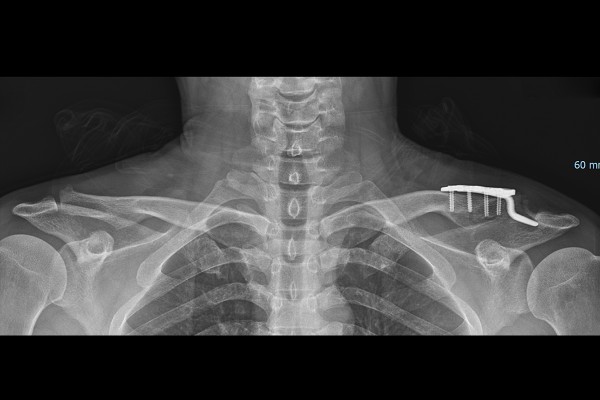

환자분께 X-RAY 및 MRI 사진을 보여드리며, 현재 어깨 상태와 함께 수술적 치료의 필요성과 방향성을 설명드렸고, 수술적 치료인 견봉-쇄골관절 탈구정복술 및 금속판 고정술, 견봉-쇄골인대 봉합 및 오구-쇄골인대 봉합술(ORIF hook plate for A-C & C-C dislocation & A-C C-C ligament repair)을 시행하였습니다.

수술은 실시간 X-RAY인 C-ARM을 이용하여 확인하면서 진행합니다. 갈고리가 달린 금속판, 후크 플레이트(Hook Plate)로 탈골된 쇄골뼈를 다시 눌러서 높이를 맞추고, 파열된 견봉-쇄골인대, 오구-쇄골인대는 봉합해줍니다.

수술 후 X-RAY에서 높이와 간격이, 탈구되기 전과 비교하였을 때, 많이 줄어든 것이 확인됩니다. 수술 후 재활과정으로는 3~4주 정도 팔걸이를 착용하여 어깨의 움직임을 제한(고정)합니다. 이후 3~4주가 지나면 팔걸이를 풀고 어깨를 들거나 흔드는 재활을 시작합니다.